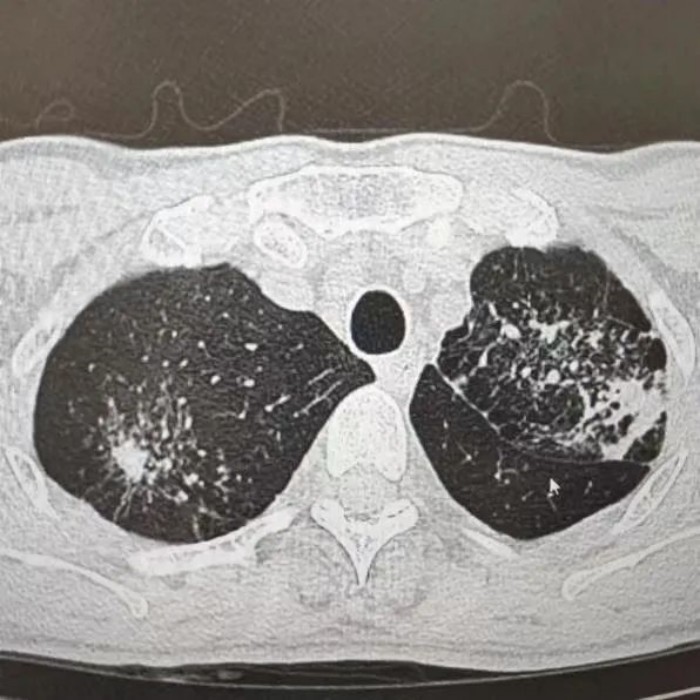

很快,CT報告提示“升結(jié)腸、回盲部及回腸末端腸壁增厚伴局部淋巴結(jié)腫大,考慮腸結(jié)核”。之后,進(jìn)一步做了胸部CT檢查,提示“肺部浸潤灶:肺結(jié)核考慮”。

經(jīng)過痰化驗及腸鏡檢查病理活檢,葉師傅被確診為“肺結(jié)核、腸結(jié)核伴腸梗阻”。